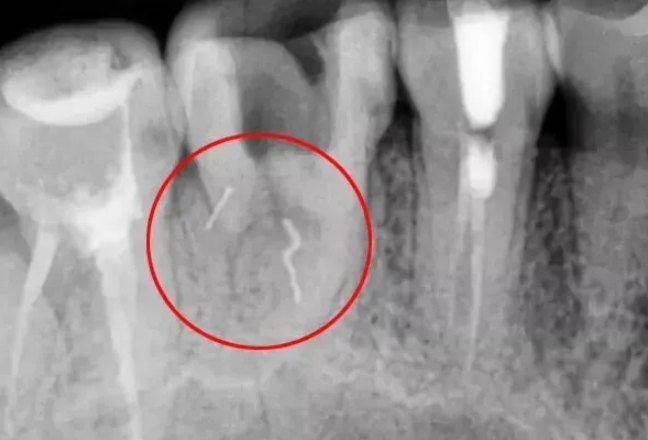

首先,发生断针的第一时间,医生会记录一些数据,包括断针的种类、型号、折断面直径、长度、折断面至标志点的距离。拍片确认根管情况。